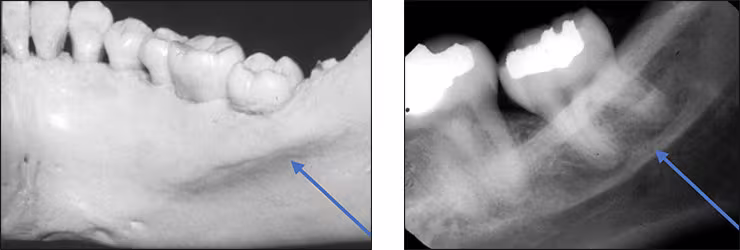

Submandibular fossa – The submandibular fossa is a depression in bone on the lingual aspect of the posterior mandible. The fossa is located bilaterally below the internal oblique ridge or mylohyoid line. This concavity is where the submandibular salivary gland rests. The submandibular fossa presents as a diffuse bilateral radiolucency typically with few trabeculae. It can appear unusually radiolucent, enticing the novice clinician into thinking a bony lesion is present. The submandibular fossa is recorded on premolar and molar periapical images. This structure is also referred to as the submandibular gland fossa or mandibular fossa.